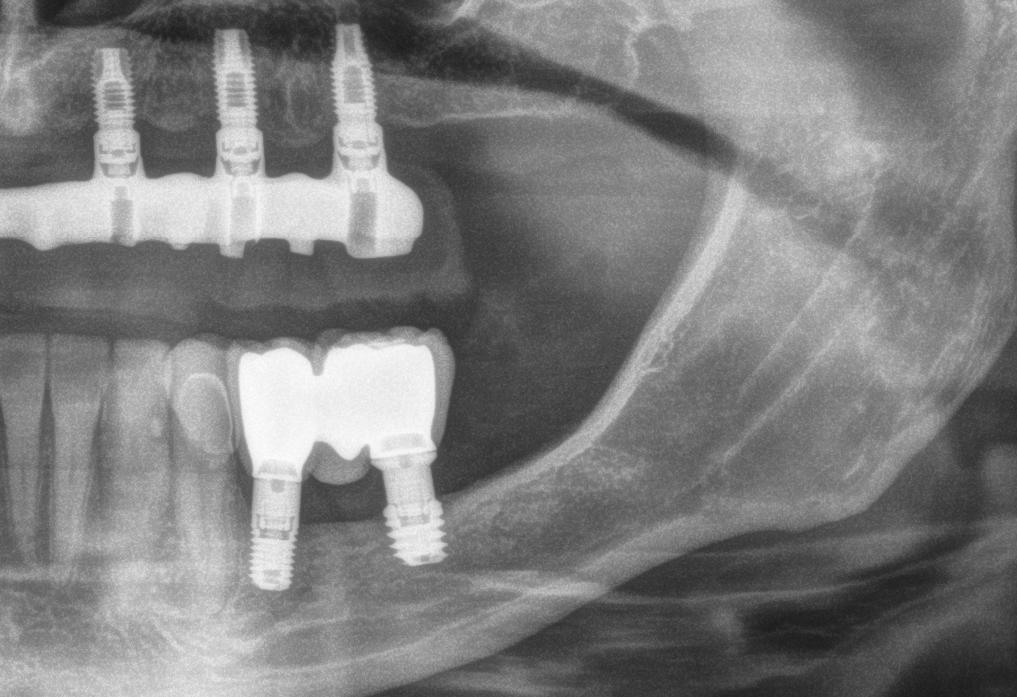

Imprescindible. Si se tuviese que definir con una palabra lo que significa el pilar Multiunit para la práctica clínica diaria en implantología, sería imprescindible. Un pilar que en su día revolucionó la manera de afrontar la rehabilitación de casos complejos y que abrió una ilimitada posibilidad de configuración de tratamientos para los clínicos y nuevas alternativas para pacientes condenados a dentaduras completas o a grandes reconstrucciones con injertos. Tanto es así que ha sido copiado por la gran mayoría de sistemas hasta convertirse en un pilar universal. Sin embargo, las exigencias estéticas de hoy en día y los conocimientos actuales de la biología en la zona trans-gingival, nos obligan a colocar los pilares en posiciones subcrestales, algo para lo que los diseños clásicos del pilar no están concebidos ni preparados. Es por ello por lo que Nobel Biocare se ha adaptado a estos requisitos y ha introducido nuevos diseños de perfiles que se adaptan mucho mejor a estas necesidades. El objetivo de esta publicación es presentar las características de los nuevos pilares y las finalidades e indicaciones de su utilización.

Introducción

Desde su inicio, los pilares Multi-unit han transformado y han formado una parte importante en la evolución de los protocolos y tratamientos en implantología de prótesis múltiple y de arcada completa. A lo largo de los años, la tecnología de los pilares ha evolucionado para mejorar su diseño, aumentar la precisión del ajuste de las restauraciones, la durabilidad y la biocompatibilidad.

Con el desarrollo de estos pilares no solamente se logra mejorar la distribución de las cargas, sino que ayudan a proporcionar una mejor inserción y ajuste de las estructuras protésicas. Así como también permiten un acceso más fácil para la limpieza y el mantenimiento. El verdadero potencial, es que gracias a los pilares Multi-unit se abre la posibilidad de realizar restauraciones más complejas gracias a su versatilidad y adaptabilidad, ofreciendo distintas alturas gingivales y varias angulaciones (17º y 30º) que ha permitido su uso en una amplia variedad de configuraciones protésicas. Tanto es así que los pilares Multi-unit han sido fundamentales en el desarrollo de tratamientos como el concepto All-on-4®,

que en su día revolucionó la manera de abordar la rehabilitación dental completa optimizando el uso del hueso disponible y reduciendo la necesidad de injertos óseos a expensas de inclinar los implantes. En resumen, los pilares Multi-unit han pasado de ser una innovación técnica para convertirse en un estándar en la implantología moderna, proporcionando soluciones efectivas y eficientes para la rehabilitación de casos complejos y mejorar significativamente la calidad de vida de los pacientes. Sin embargo, hoy en día, el pilar Multi-unit se ha convertido en un pilar exigido. Originalmente fue creado para ser rehabilitado a nivel yuxtagingival en tramos edéntulos donde existía una configuración “plana” de la encía. Para seleccionar la colocación del pilar simplemente se debía medir la altura de la encía y calcular la angulación del implante con respecto a la emergencia de los dientes para determinar la necesidad de utilizar un pilar angulado. Con la evolución de la implantología, los conceptos de planificación protésicamente guiada, las filosofías de “cero pérdida ósea” (zero bone loss concepts, Linkevicius [Ref.1]) y los conocimientos de la estética actual sobre implan-

tes están presentes a la hora de colocar los implantes y rehabilitarlos. El objetivo ya no es buscar una rehabilitación funcional, sino que también es lograr una apariencia estética natural duradera y estable a lo largo del tiempo evitando problemas como la recesión gingival o la pérdida ósea marginal e interproximal. El nivel de conocimiento que existe en implantología unitaria implica tal cantidad de conceptos y detalles a nivel biológico y protésico que dificulta mucho y hace prácticamente imposible la utilización de los pilares Multi-unit clásicos para situarlos en la zona transgingival y lograr emergencias estéticas adecuadas. Como siempre, Nobel Biocare ha comprendido estas necesidades y se ha adaptado a estos requisitos introduciendo nuevos diseños de perfiles que se adaptan mucho mejor a este tipo de situaciones y resultados. El objetivo de esta publicación es presentar las características de los nuevos pilares Multi-unit y sus finalidades, así como también las indicaciones de su utilización.

Limitaciones de los pilares Multi-unit clásicos en la zona transgingival

La importancia en la preservación del hueso crestal alrededor de los implantes y de las distintas estructuras del fenotipo periimplantario es vital para el mantenimiento y éxito funcional y estético a largo plazo (Ref.2). La utilización de conexiones cónicas robustas, mecánicamente estables y con cambio de plataforma como las de NobelActive® y NobelParallel™ pueden ayudar al mantenimiento del hueso crestal (Ref.3). Sin embargo, también es importante asociar este tipo de conexiones con la posición tridimensional del implante (Ref.4). Concretamente en el plano apico-coronal, la colocación de los implantes en posiciones subcrestales va a ayudar no solo a mantener el hueso, sino que va a permitir generar el espacio necesario para establecer una zona de transición biológica y protésicamente necesaria para desarrollar los perfiles de emergencia adecuados hasta llegar a la anatomía del margen gingival de la corona o perfil crítico (Ref. 5). Según las publicaciones, este espacio está establecido 3 ,5-4mm del margen gingival (Ref.6, Ref.7).

Desde el punto de vista restaurador en implantes unitarios, es conocido que estos perfiles de emergencia deben ser diseñados con una transición suave. Partiendo desde un diámetro estrecho que progresivamente se va ensanchando. Siempre que el implante esté bien colocado tridimensionalmente el resultado será un perfil de emergencia cóncavo en

el área subgingival. (Refs.8,9,10). La finalidad del concepto es proporcionar el máximo espacio horizontal para el crecimiento de tejido conectivo supracrestal alrededor de la interfase de titanio o pilar personalizado ofreciendo protección al implante a costa de maximizar el grosor y estabilidad a las estructuras del fenotipo periimplantario (Ref.11). El verdadero reto surge en situaciones en las que es posible crear una prótesis múltiple del tipo FP1 (Ref.12), donde siempre se debe utilizar un pilar Multi-unit. Cuando se utiliza un implante asociado a este tipo de pilar para crear una emergencia natural desde la encía, éste se debe planificar teniendo en cuenta que el volumen del pilar va a ocupar prácticamente toda el área de la altura de tejido supracrestal (“Suprecrestal tissue height” Ref. 11) y debe estar “camuflado” en dicha zona de transición ocupando gran parte del espacio para el tejido conectivo supracrestal y del perfil de emergencia de la restauración (Ref. 13). Ya sea un pilar recto o angulado, debido a sus formas robustas y perfiles anchos, resulta difícil de planificar su colocación en zonas estéticas ya que el complejo implante-pilar se va a comportar como un implante tipo “tissue level” (Ref.14) (Fig.1). Con los diseños clásicos de pilares no se van a poder respetar las concavidades subgingivales deseadas y siempre va a implicar la eliminación de hueso, sobre todo a nivel interproximal y vestibular en la zona del cenit del diente (Ref.15) (Fig.2). Las consecuencias automáticas serán picos de hueso interproximales reducidos, papilas más cortas y dientes con cenits más planos y anchos en el tercio gingival. Incluso en situaciones de implantes adyacentes puede provocar la pérdida o ausencia total de papila interimplantaria (Ref.7) (Fig.3).

Innovaciones y características del nuevo pilar

Multi-unit: perfiles para preservar

Debido a esta compleja situación, se ha desarrollado una nueva línea de pilares Multi-unit que rompe con los diseños clásicos y que se presenta a continuación: (Figs. 4,5).

Con respecto al Multi-unit recto, su principal característica es la emergencia desde la plataforma del implante con un perfil completamente cóncavo. Por una parte, va a maximizar el efecto de “cambio de plataforma” en su parte más crestal a nivel de la plataforma del implante y por otra va a facilitar mucho más espacio para la creación de tejido conectivo supracrestal a lo largo de toda la transición hasta la plataforma restauradora. El perfil cóncavo

del pilar también respetará en mayor medida los espacios comprendidos entre el pilar y el hueso interproximal (en el caso de una colocación subcrestal entre 1,5 y 2mm) para poder preservar al máximo las estructuras anatómicas presentes que soportarán las papilas periimplantarias.

Así como el diseño clásico de pilar hacía prácticamente imposible la colocación de implantes inmediatos en zona estética, el nuevo perfil cónca-

vo del pilar Multi-unit hace que se convierta en un pilar ideal para estas situaciones. La altura de pilar de 3 ,5 mm, hace que se pueda colocar la plataforma del implante en la posición corono-apical deseada con respecto al margen gingival sin involucrar el hueso adyacente y permitiendo desarrollar un mínimo perfil de emergencia restaurador más horizontal para soportar cenit y tejido interproximal. (Fig.6-7) Otra característica de diseño importante es la reducción del bisel de la plataforma restauradora tanto en los pilares rectos como en los pilares angulados. Sin cambiar su diámetro clásico de 4,8mm ni su compatibilidad para atornillar y asentar cualquier aditamento restaurador de toda la gama Multi-unit, el nuevo pilar presenta una plataforma mucho más fina y estilizada que facilitará también su inserción incluso sin necesidad de utilizar la fresa “bone mill” o molinillo de hueso. De esta manera no solo se seguirá incrementando la preservación ósea, sino que también se reducirán los tiempos quirúrgicos al evitar tener que atornillar y desatornillar la guía del molinillo o “Bone Mill Guide”. (Figs. 8-12)

Multi-unit angulado: “de tractor a deportivo”

12 nuevo, esta forma comulga mucho más con los conceptos mencionados anteriormente. Además, proporcionará un verdadero impacto en la manera de planificar y en los resultados a largo plazo. Seguidamente se describen algunos ejemplos clínicos para las angulaciones de 30º y 17º respectivamente:

Sin duda, los perfiles mejorados del Multi-unit recto aportan beneficios claros e inmediatos que facilitarán la práctica clínica, pero el pilar que realmente revoluciona e innova es el nuevo pilar angulado. (Fig.13)

En esta ocasión se ha logrado reducir el tamaño del robusto pilar original a la mínima expresión, obteniendo líneas suaves, finas y redondas. De

La colocación del implante inclinado de 30º siempre implica que la zona más mesial de la plataforma se encuentra en posición yuxtaósea y la zona distal en posición subcrestal. Clásicamente se debe utilizar el instrumento “bone mill” de 5,2mm (NP) o 6,2mm (RP) para poder insertar el pilar en la posición deseada. En la figura 14 (Fig.14) se observa una situación clínica comparativa donde se han colocado implantes inclinados con una orientación de 30º aproximadamente en dirección hacia los rebordes piriformes en una premaxila. Claramente se puede observar la cantidad de remodelación ósea provocada por el molinillo versus la preservación que ofrece la colocación el nuevo Multi-unit sin necesidad de acondicionar la cresta ósea. En configuraciones de tipo All-on-4®, en los implantes distales se

produce una situación similar. El inconveniente que se puede producir en estos casos es la posibilidad de la aparición de una recesión de la mucosa periimplantaria alrededor del pilar precisamente por la combinación de quedar la zona sin soporte óseo y por el propio volumen excesivo que ocupa el pilar. Por el contrario, mediante la utilización de los nuevos perfiles no existe necesidad de remodelar el reborde alveolar y conjuntamente al menor volumen que ocupan los pilares, el tejido (si es suficiente) será capaz de mantenerse en mayor medida. En las figuras 15 a 18 (Fig.15-18) se describe una situación común donde se utiliza el pilar Multi-unit de 17º. En pacientes edéntulos o futuramente edéntulos en la zona de la premaxila. Para maximizar el hueso disponible en esta zona y poder lograr un adecuado torque de inserción es recomendable colocar los implantes en la orientación del hueso, que la gran mayoría de veces discurre en la misma dirección de los bordes incisales de los dientes anteriores. Para compensar y llevar la emergencia de los accesos de los tornillos protésicos hacia palatino se utiliza un pilar Multi-unit de 17º. El dilema en esta zona recae en qué altura de pilar utilizar. Si se utiliza un pilar de 3,5mm de altura, existe el riesgo de reducir el espacio protésico y de nuevo que aparezca una recesión gingival si el implante se coloca a nivel crestal o ligeramente subcrestal (1-1,5mm). Independientemente de la altura seleccionada (2,5mm o 3,5mm), de nuevo, esta situación implica la remodelación ósea mediante bone mill para acomodar el pilar. En la Fig.10 se observa cómo queda la remodelación circular en el implante en posición #1.2 versus la no remodelación de un pilar de nuevo perfil de altura 3,5mm en un implante colocado 2mm subcrestal. La limitación de los pilares de 17º clásicos es que emergen muy rápidamente hacia el diámetro de 4,8mm de la plataforma restauradora y de nuevo no existe espacio suficiente para el establecimiento biológico de la altura de tejido supracrestal. Claramente se observa en las radiografías periapicales comparativas a los 3 meses de la colocación como el implante en posición #1.2 tiene signos de remodelación fisiológica. Hecho que no ocurre en los pilares con nuevos perfiles al ofrecer transiciones más suaves que respetan los principios biológicos.